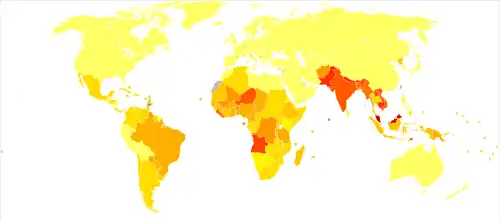

.png)

In 2018, 208,619 new cases of leprosy were recorded, a slight decrease from 2017.[100] In 2015, 94% of the new leprosy cases were confined to 14 countries.[101] India reported the greatest number of new cases (60% of reported cases), followed by Brazil (13%) and Indonesia (8%).[101] Although the number of cases worldwide continues to fall, there are parts of the world where leprosy is more common, including Brazil, South Asia (India, Nepal, Bhutan), some parts of Africa (Tanzania, Madagascar, Mozambique), and the western Pacific.[101] About 150 to 250 cases are diagnosed in the United States each year.[102]

In the 1960s, there were tens of millions of leprosy cases recorded when the bacteria started to develop resistance to dapsone, the most common treatment option at the time.[4][14] International (e.g., the WHO's "Global Strategy for Reducing Disease Burden Due to Leprosy" and the International Federation of Anti-Leprosy Associations) and national initiatives have reduced the total number and the number of new cases of the disease.[14][103]

The number of new leprosy cases is difficult to measure and monitor because of leprosy's long incubation period, delays in diagnosis after the onset of the disease, and lack of medical care in affected areas.[104] The registered prevalence of the disease is used to determine disease burden.[105] Registered prevalence is a useful proxy indicator of the disease burden, as it reflects the number of active leprosy cases diagnosed with the disease and receiving treatment with MDT at a given point in time.[105] The prevalence rate is defined as the number of cases registered for MDT treatment among the population in which the cases have occurred, again at a given point in time.[105]